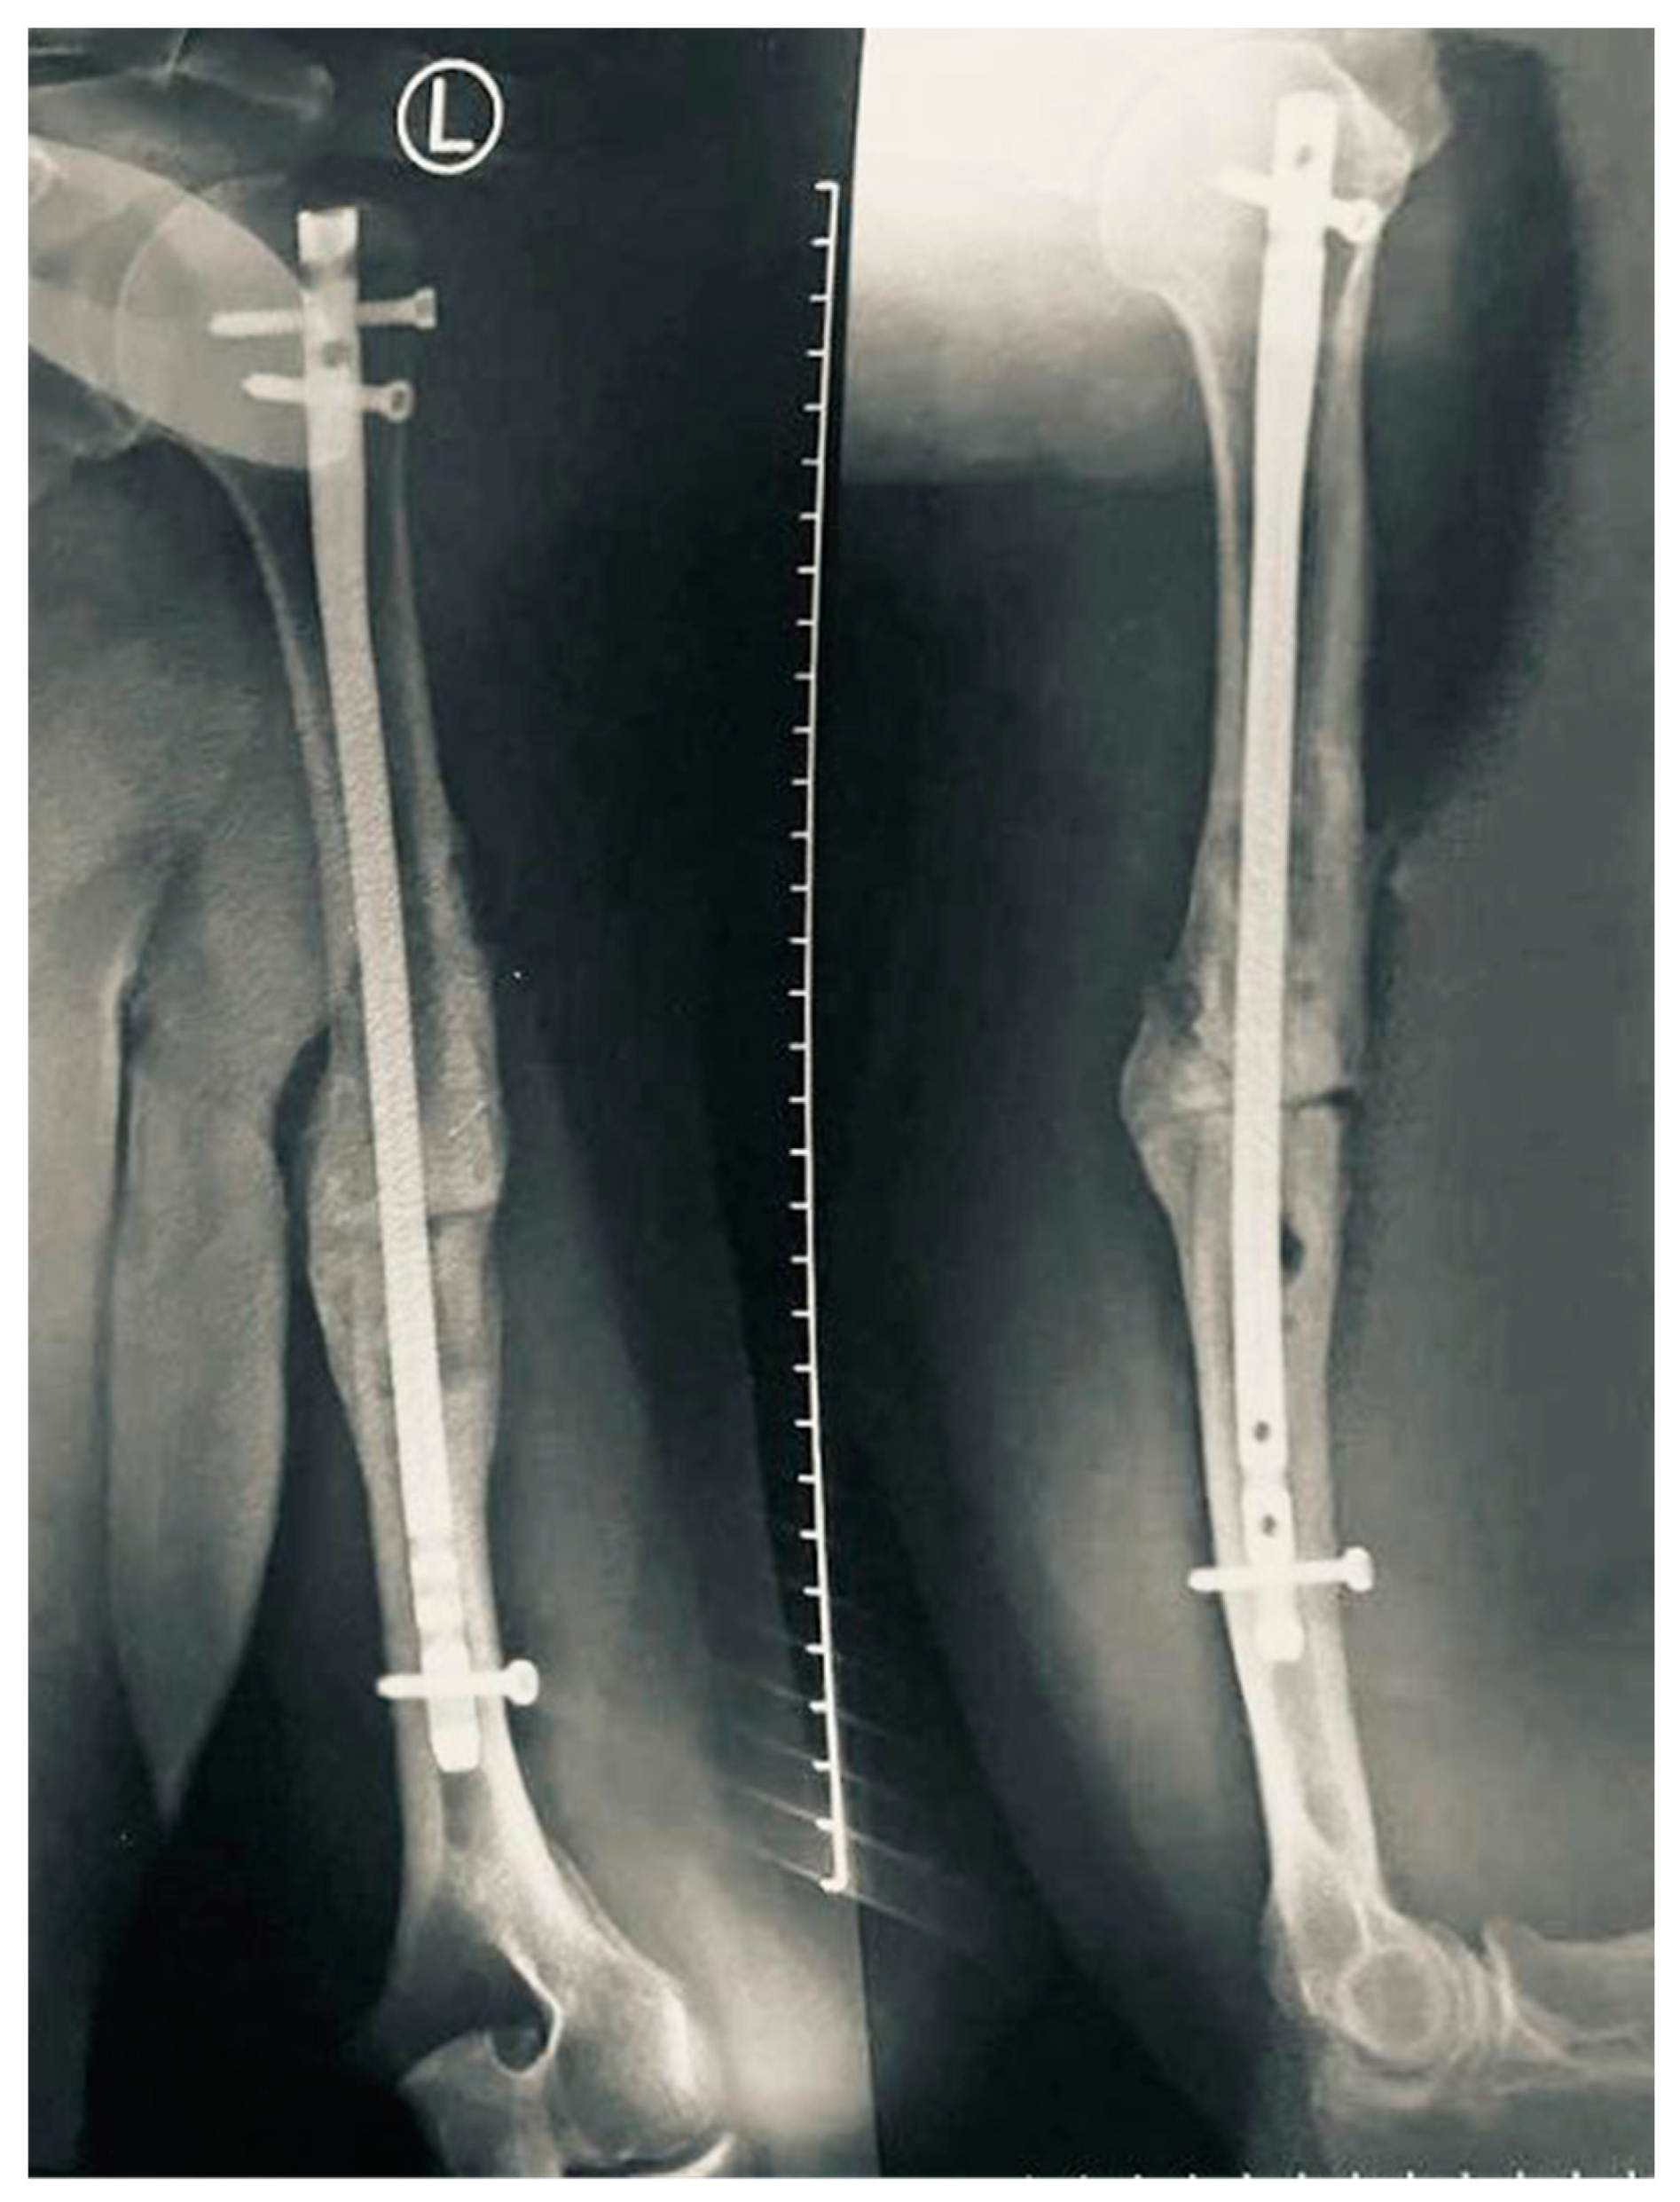

Anterograde Intramedullary Nailing without Bone Grafting for Humeral Shaft Nonunion Associated with Early Exploration of Secondary Radial Nerve Palsy: A Case Report

2. Case Report